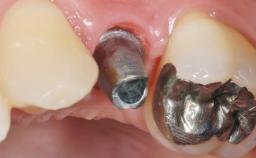

Early Placement of an Implant in a Maxillary Right Central Incisor Site

Abutment Type Customized

Prosthesis Type FDP

Loading Protocol Conventional or early

Retention Cemented, with prosthesis margin < 3mm submucosal Cemented, with prosthesis margin < 3mm submucosal

Provisional Implant-Supported Prosthesis Prosthodontic margin < 3 mm apical to mucosal margin Prosthodontic margin < 3 mm apical to mucosal margin